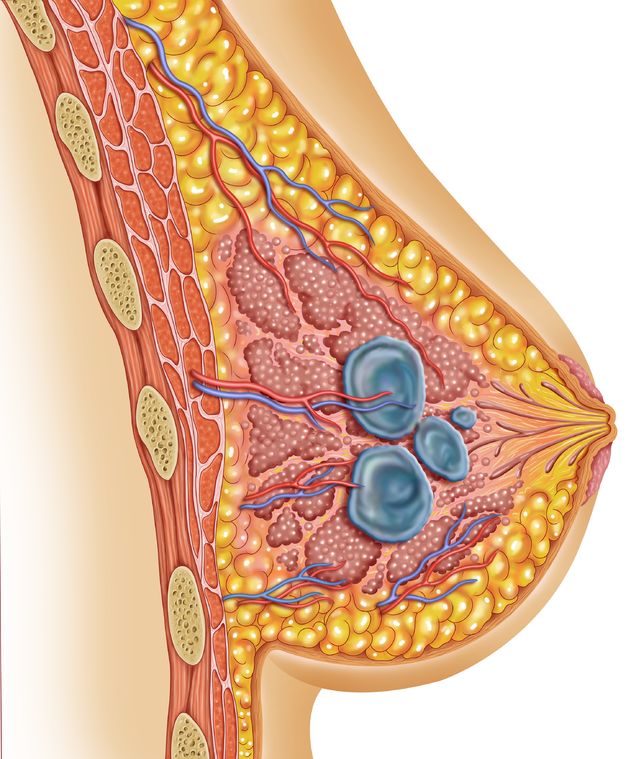

Breast Ultrasound

Bilateral $175 (costs include a report from the Radiologist)

Bilateral $175 (costs include a report from the Radiologist)

Unilateral $95 (costs include a report from the Radiologist)

This ultrasound exam can provide you and your health care provider an assessment of your breast health. A breast ultrasound can locate breast tumors and cysts as small as a few millimeters in size and is a beneficial screening for women who have dense breasts. Breast ultrasounds are considered safe and painless. Women who use our services are:

Those that do not want to wait for their physicians/insurance referral

Those that do not want the radiation exposure from a mammogram

Cash paying patients or those that have PPO insurance